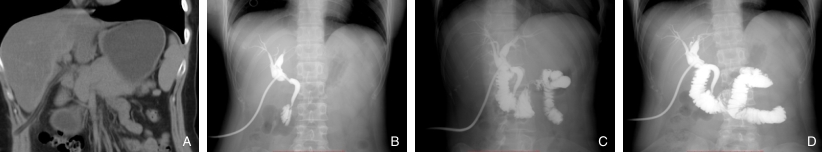

图2 胆总管内异物(Hem-o-lok夹)及术中取出实物 A-C:经胆总管切口取出Hem-o-lok夹;D:3枚Hem-o-lok夹Fig.2 Foreign bodies (Hem-o-lok clips) in the common bile duct and the specimens retrieved during surgery A-C: Hem-o-lok clips extracted through the choledochotomy incision; D: The three Hem-o-lok clips